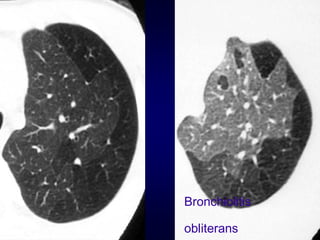

Bronchiolitis obliterans (constrictive bronchiolitis)

idiopathic, connective tissue diseases, drug reaction,

after transplantation, after infection

Bronchiolitis

obliterans